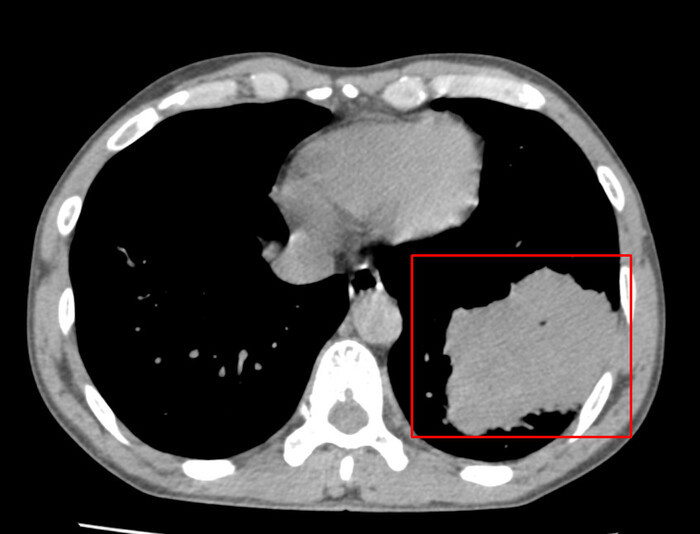

Kết quả kiểm tra cho thấy phim chụp CT lồng ngực của bệnh nhân có hình ảnh khối u thùy dưới phổi trái kích thước 73 mm x 80 mm. Người bệnh rất bất ngờ với kết quả khám của mình.